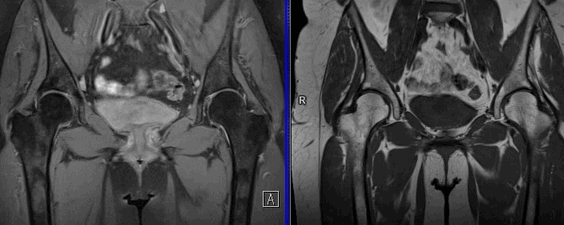

(Слева) Рентгенография в ПЗ проекции: наблюдается выраженный остеонекроз. Признаки включают неоднородный склероз и умеренный коллапс суставной поверхности. При боковой локализации очага риск развития коллапса выше, чем при его срединном положении.

(Справа) Рентгенография в ПЗ проекции: остеонекроз бедра с выраженным коллапсом суставной поверхности. При развитии коллапса хирургические возможности лечения ограничиваются либо геми-артропластикой, либо тотальным эндопротезированием тазобедренного сустава. Умеренное верхнее сужение суставного пространства говорит о развитии вторичного остеоартрита. (Слева) Рентгенография нижней конечности в положении отведения в боковой проекции: визуализируется обширный субхондральный перелом. Такая находка должна привлекать внимание к суставной поверхности, которая, в данном случае, умеренно запала.

(Справа) Рентгенография тазобедренного сустава в косой проекции, другой пациент: умеренный склероз и коллапс передне-верхнего опорного участка головки бедренной кости. Передне-верхняя локализация является наиболее частой при остеонекрозе и небольшие изменения лучше отображаются в боковой проекции с отведением ноги или в косой проекции. (Слева) Рентгенография в ПЗ проекции: картина остеонекроза с последующим субкапитальным переломом шейки бедренной кости и его фиксацией. Крупный очаг инфаркта привел к выраженному уплощению головки. Имеет место вторичный остеоартрит с сужением суставного пространства и остеофитами.

(Слева) Фронтальная Т1ВИ МР-И, ранние изменения, указывающих на остеонекроз. Лентовидные очаги низкого сигнала в Т1ВИ в передней части головок обеих бедренных костей.

(Справа) Сагиттальная Т1ВИ МР-И: остеонекроз в большом сегменте передней части головки бедренной кости. Линия низкого сигнала отграничивает нормальную костную ткань от инфарктной. В очаге инфаркта кость сохраняет нормальный сигнал от жира. Отек присутствует в нормальном коаном мозге, прилегающем к очагу. Отечности костного мозга сопутствует боль и угрожающий коллапс. (Слева) Аксиальная Т2ВИ FS МР-И с признаком двойной лини: полоса низкого сигнала прилегает к нормальной кости, в зоне репарации определяется яркий сигнал. Этот признак необходим для подтверждения диагноза. Аксиальная проекция менее всего подходит для выявления коллапса суаавной поверхноаи, который, как правило, вовлекает верхнюю ее часть.

(Справа) Фронтальная Т2ВИ FS МР артрография: субхондральный серповидный перелом, вовлекающий 50% верхней суставной поверхности. Заболевание клинически не проявлялось и было соотнесено с употреблением алкоголя. (Слева) Фронтальная PD FSE FS МР-И: небольшой субхондральный перелом, неровность суставной поверхности и выступающий гиперинтенсивный отечный учааок коаного мозга в головке и шейке бедренной коаи. Такой учааок коаного мозга наиболее характерен для III стадии заболевания и ему часто сопутавует болевой синдром.

(Справа) Фронтальная STIR МР-И: яркие линии при признаке двойной линии, отек костного мозга значительный выпот в суставе. Аспирация суставного выпота может уменьшить боль.